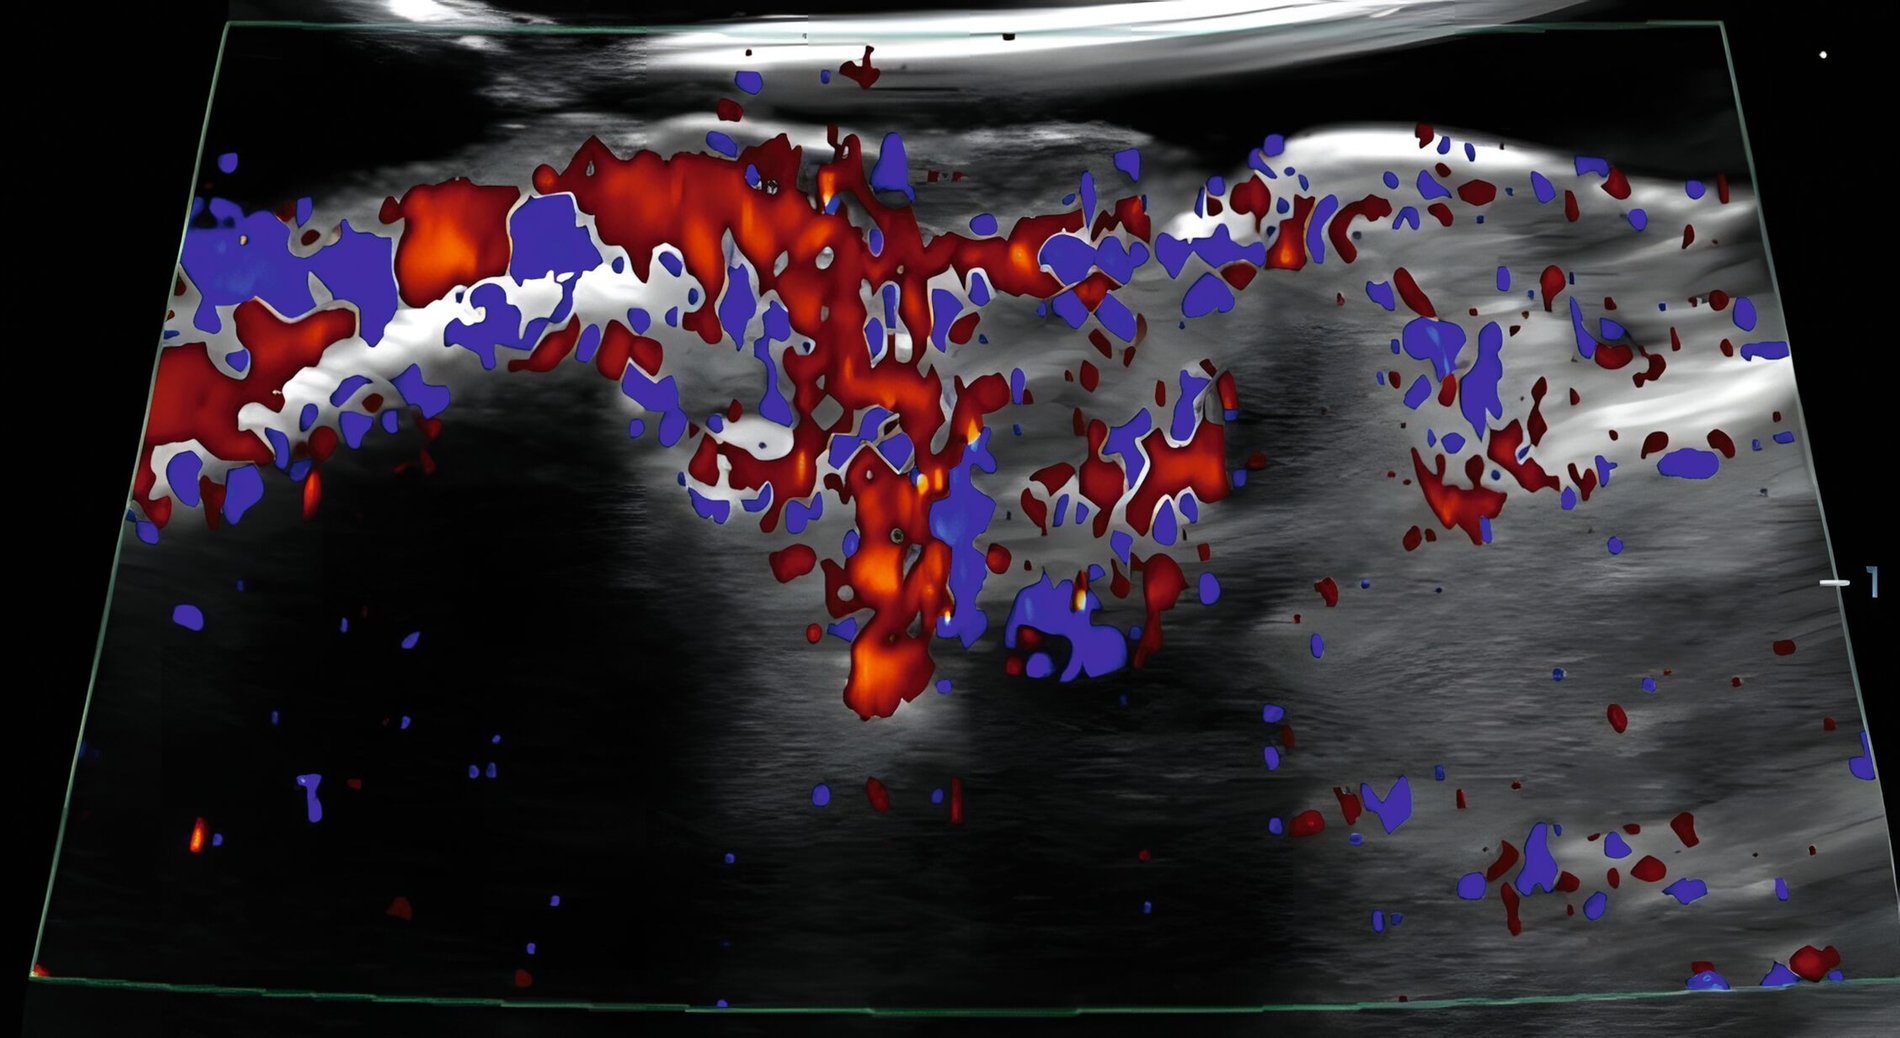

In klinischen Studien konnte gezeigt werden, dass die Sonografie des oralen Weichgewebes zur Beurteilung der dynamischen Gewebeperfusion und von Blutflussschwankungen angewendet werden kann [Chan et al., 2020; Barootchi et al., 2022; Chan & Kripfgans, 2020; Tavelli et al., 2023]. Am Implantat wurde in einer klinischen Studie erstmals mit einer 30-MHz-US-Sonde (ZS3, L30-8, Mindray, Mountain View CA, USA) die Differenzierung zwischen periimplantärer Gesundheit und Erkrankungen beschrieben [Chan et al., 2020] (Abbildung 9).

In einer weiteren klinischen Studie wurde die Aussagekraft der funktionellen Sonografie des periimplantären Weichgewebes bei Implantaten mit unterschiedlichen klinischen Diagnosen (gesund, periimplantäre Mukositis oder Periimplantitis) untersucht [Barootchi et al., 2022]. Der US-Farbfluss konnte die periimplantäre Durchblutung messen und die US-Messungen stimmten mit den klinischen Diagnosen überein.

Zusammenfassend zeigen die Ergebnisse, dass die funktionelle Sonografie (Gewebeperfusion und Blutflussschwankungen) zur Differenzierung des oralen, weichgewebigen Entzündungsgrades angewendet werden kann.

Neben der anatomischen Darstellung wird auch die funktionelle Bildgebung zur Beurteilung der Gewebedurchblutung mittels Farbfluss (traditionell Farb-Doppler genannt) intensiv untersucht. In klinischen Studien konnte die Sonografie zur Differenzierung parodontaler und periimplantärer Erkrankungen erfolgreich angewendet werden.